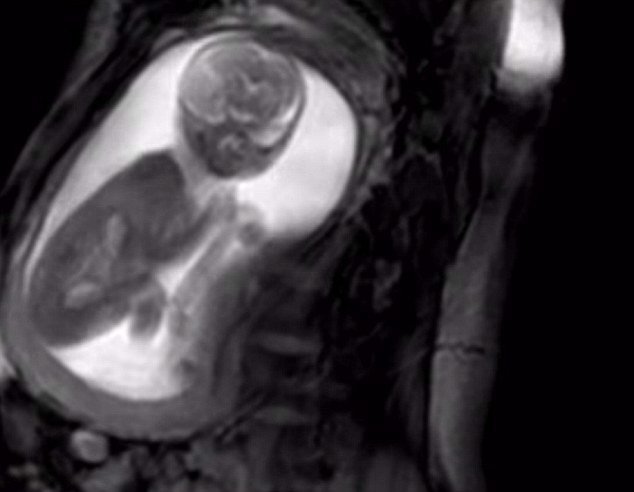

تاکنون والدین برای دیدن نوزاد متولد نشده خود از سونوگرافی استفاده میکردند که تصاویری سیاه و سفید و با کیفیت معمولی را به آنها ارائه میکند اما با این فناوری جدید آنها این شانس را خواهند داشت تا قلب جنین 20 هفتهای خود را با استفاده از اسکن فوقالعاده پیشرفته در تصاویری با وضوح بسیار بالا تماشا کنند.